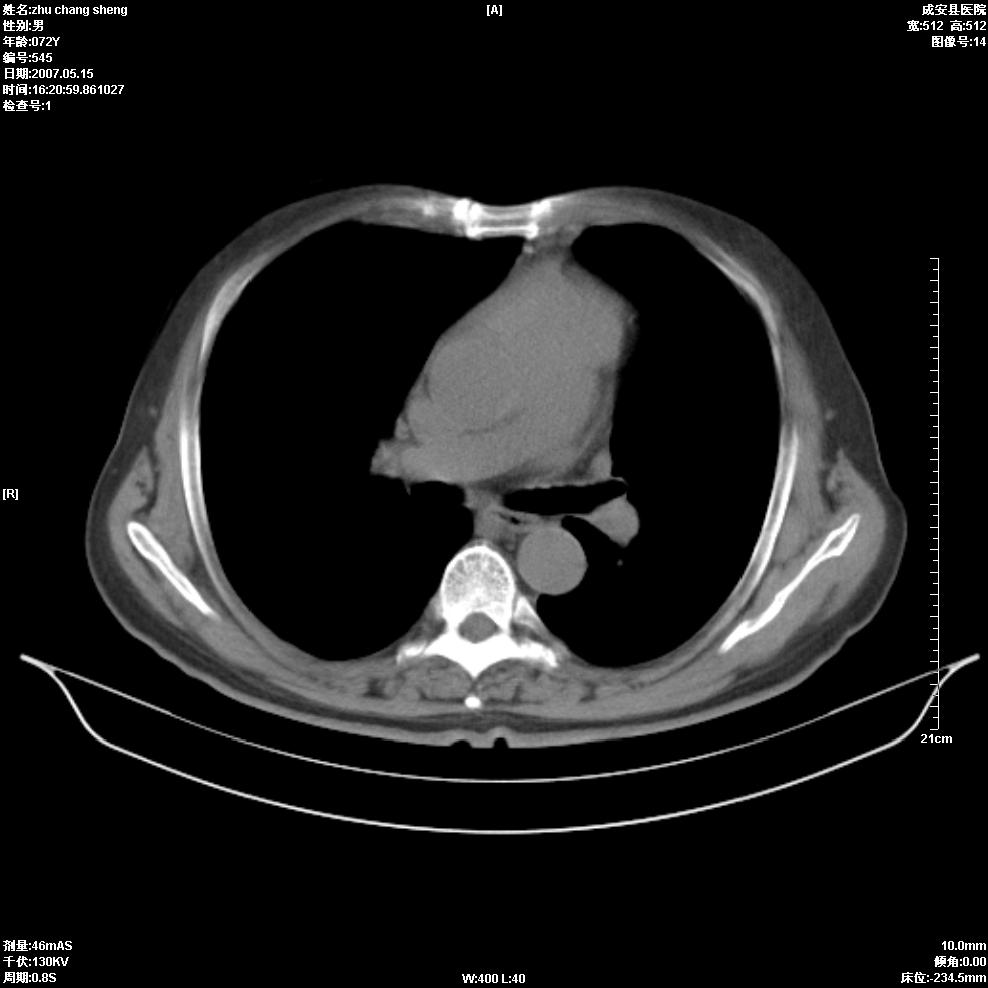

以下是引用医博云天在2007-5-15 19:10:00的发言:[br]心包积液,胸腔积液,心影增大,左心为主。

以下是引用zhangzhongshou在2007-5-15 20:21:00的发言:[br]心包积液可以肯定有,肿块显示不清,建议增强或mri检查。

以下是引用拾荒者在2007-5-15 22:28:00的发言:[br]心包膜增厚,有少量积液,右室前壁示均匀软组织密度影,边界欠清,建议增强扫描或mri检查与室壁瘤鉴别。

以下是引用还珠格格在2007-5-19 9:50:00的发言:[br]病人与5月18日 做了核磁增强扫描 确诊为前上纵隔侵袭性胸腺瘤。